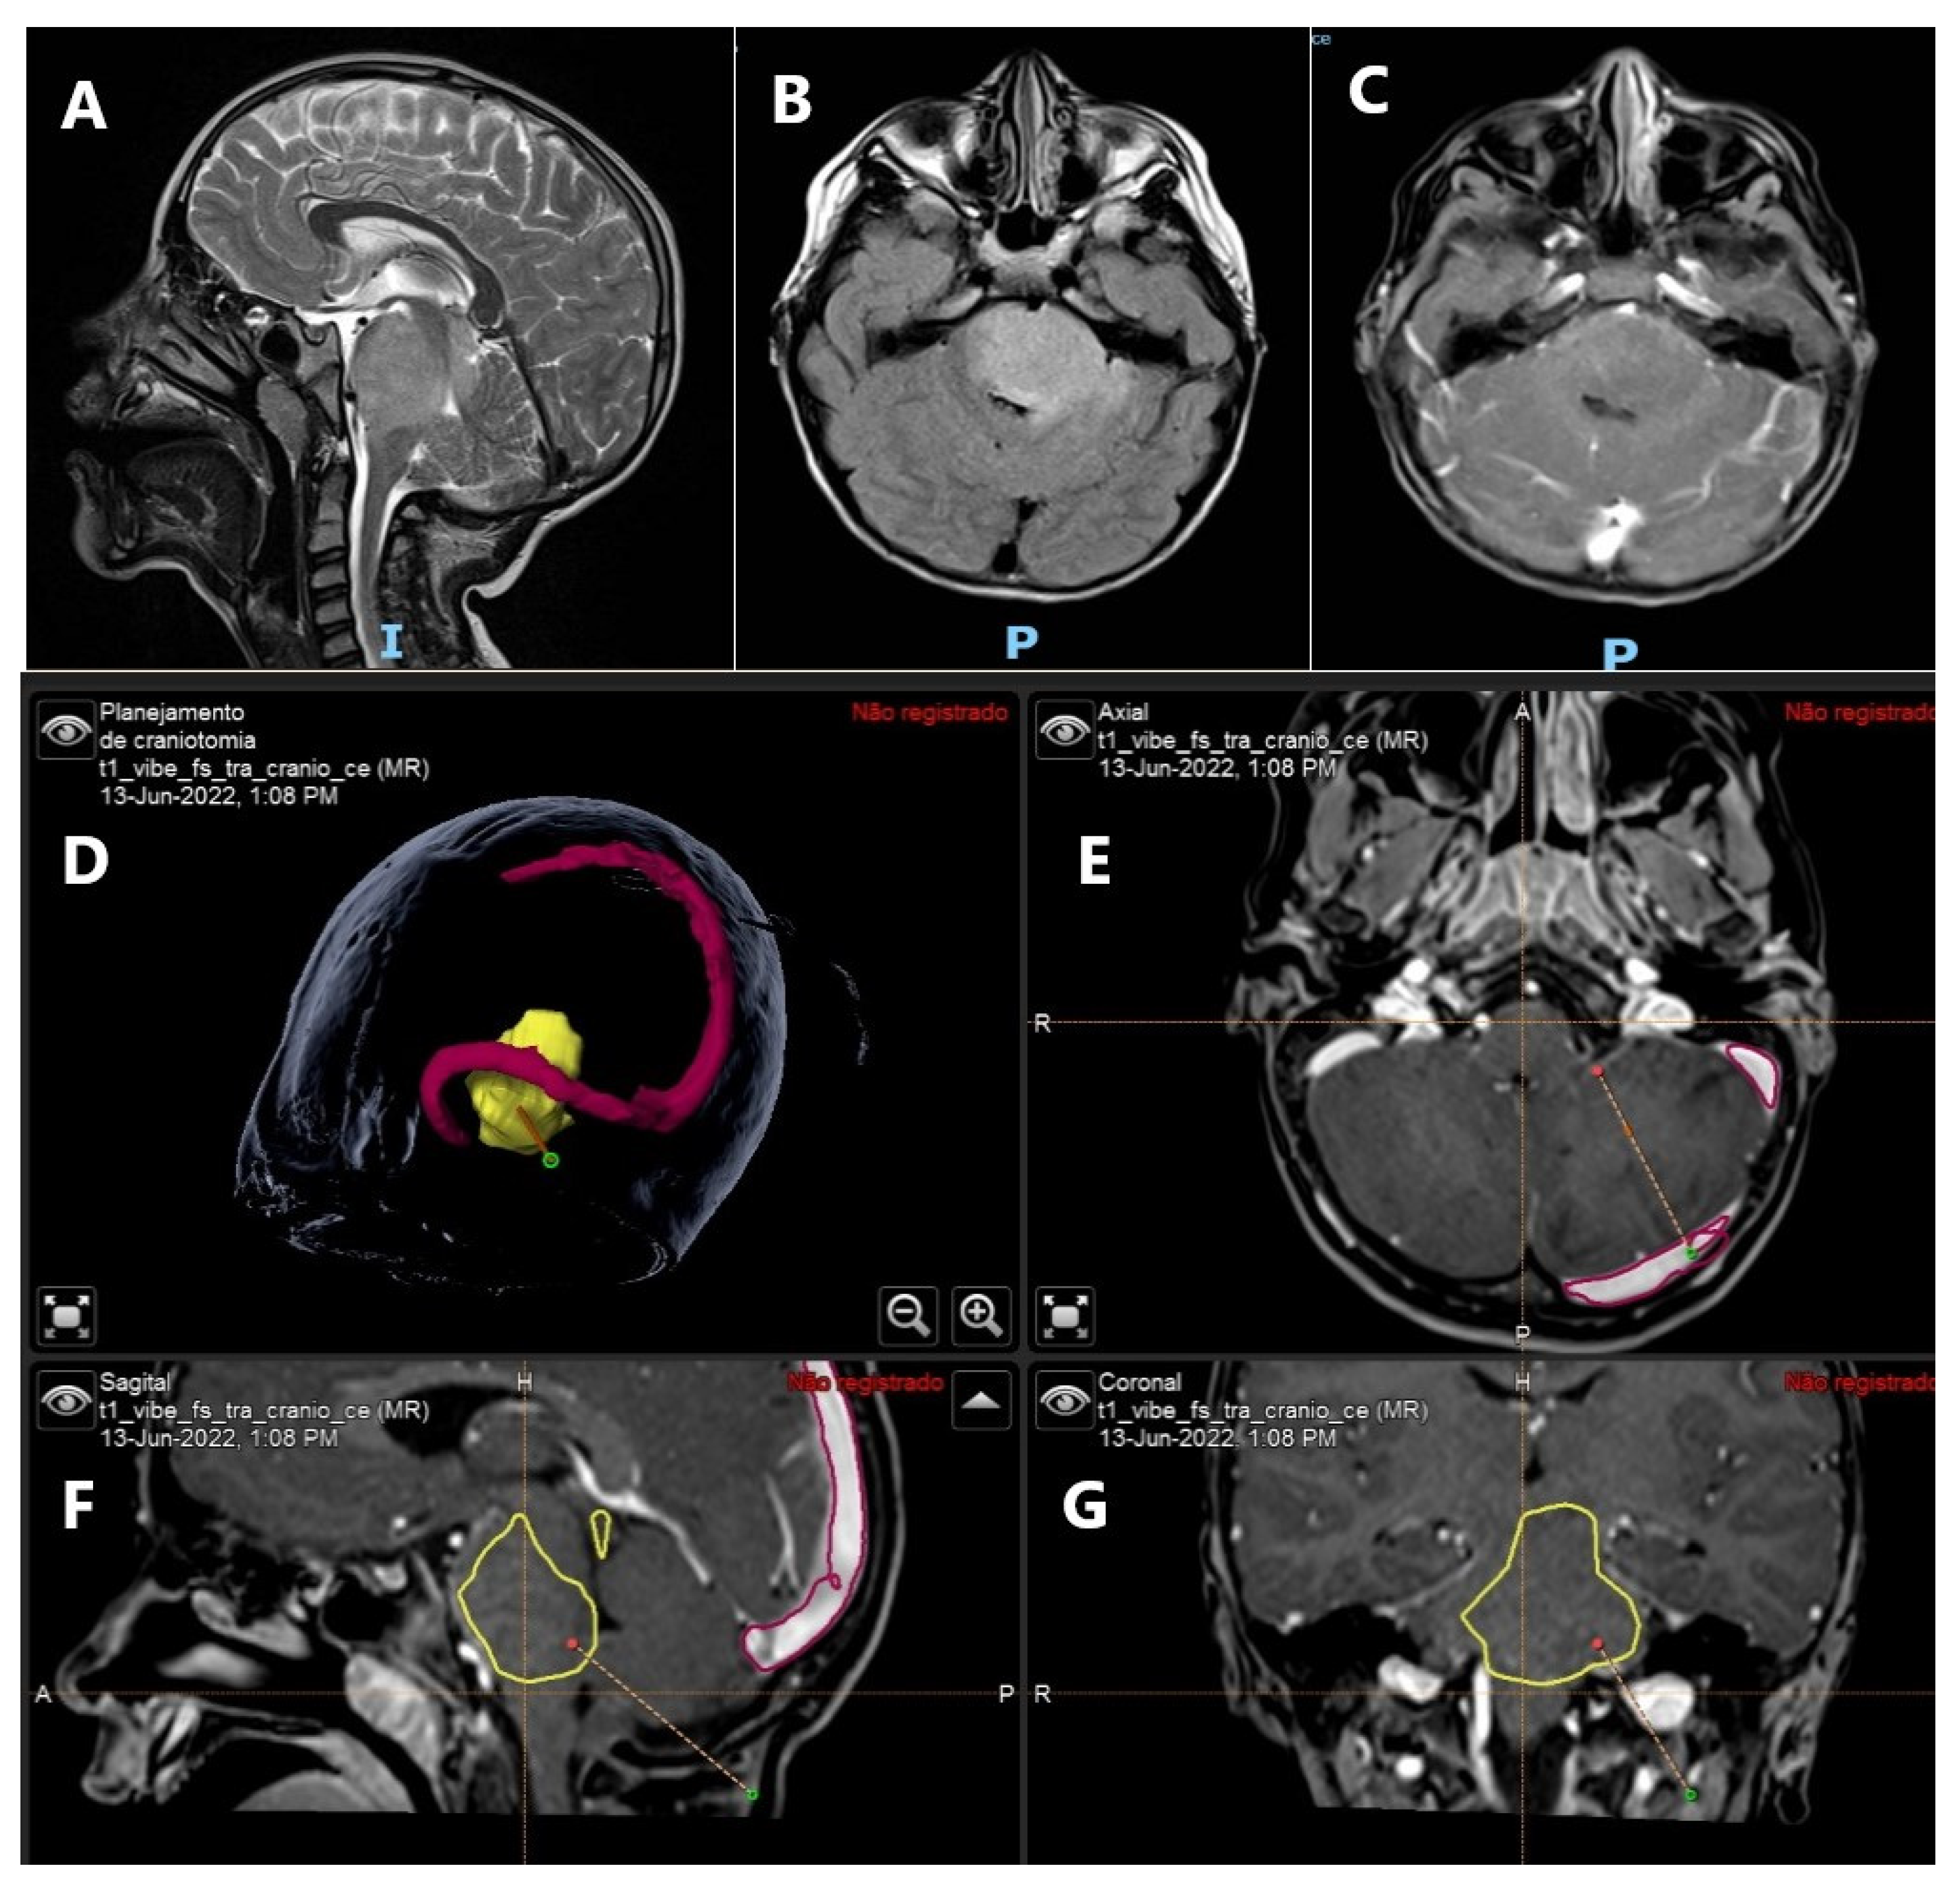

- Shioyama, T.; Muragaki, Y.; Maruyama, T.; Komori, T.; Iseki, H. Intraoperative flow cytometry analysis of glioma tissue for rapid determination of tumor presence and its histopathological grade: Clinical article. J. Neurosurg. 2013, 118, 1232–1238. [Google Scholar] [CrossRef]

- Vartholomatos, E.; Vartholomatos, G.; Alexiou, G.; Markopoulos, G. The Past, Present and Future of Flow Cytometry in Central Nervous System Malignancies. Methods Protoc. 2021, 4, 11. [Google Scholar] [CrossRef]